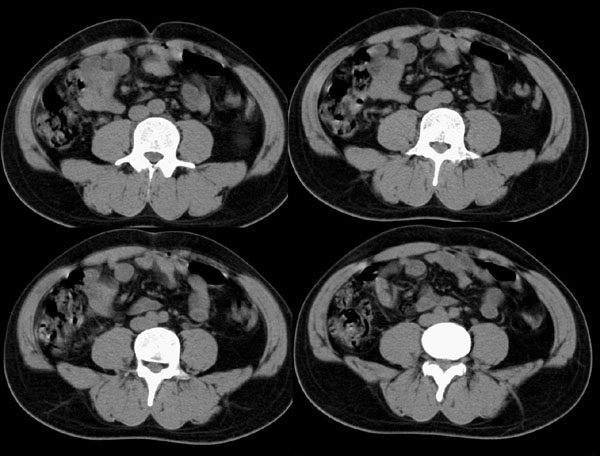

左输尿管上端狭窄(先天性,或血管压迫所致)伴肾积水.

左侧肾盂、肾盏扩张,肾盂输尿管移行部突然狭窄,未见明显占位及高密度结石影,体检发现,考虑:先天性肾盂输尿管移行部狭窄。(原因多方面,有先天缺陷造成移行部结构异常或因为迷走血管、纤维索条引起肾盂输尿管的压迫扭曲所致。)大剂量ivp或肾盂造影有助于显示输尿管狭窄部位及形态。

支持!建议逆行造影或穿刺顺行造影进一步检查。